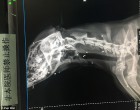

A férfi azonnal állatorvoshoz vitte barátját, ahol megállapították, hogy legalább 50-szer lőttek bele légpuskával a kutyába, ami gazdája szerint egyértelműen állatkínzás. Szavait a röntgenfelvételek is alátámasztják, melyeken többek között az is látszik, hogy lövedék fúródott Er Mao agyába és az egyik szemébe is.

A kutya majdnem két hónap alatt, három sebészeti műtéten esett át, mire kiengedhették a kórházból. Megpróbáltak annyi lövedéket eltávolítani a testéből amennyit csak lehetett, de így is maradt 9, amit túl kockázatos lett volna kivenni, beleértve azt a golyót is ami a szemén keresztül fúródott az agyába.